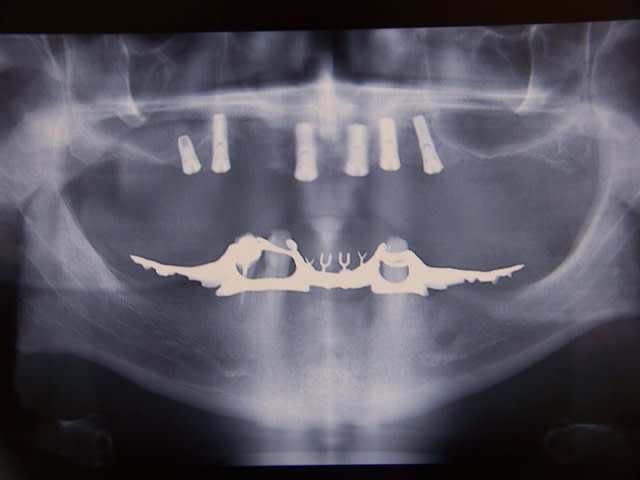

y a une belle gencive

Positdental 10 cpzr2n - Eugenol

mince trop tard pxav

2010.05 - Eugenol

y n'a plus qu'il n'y parait